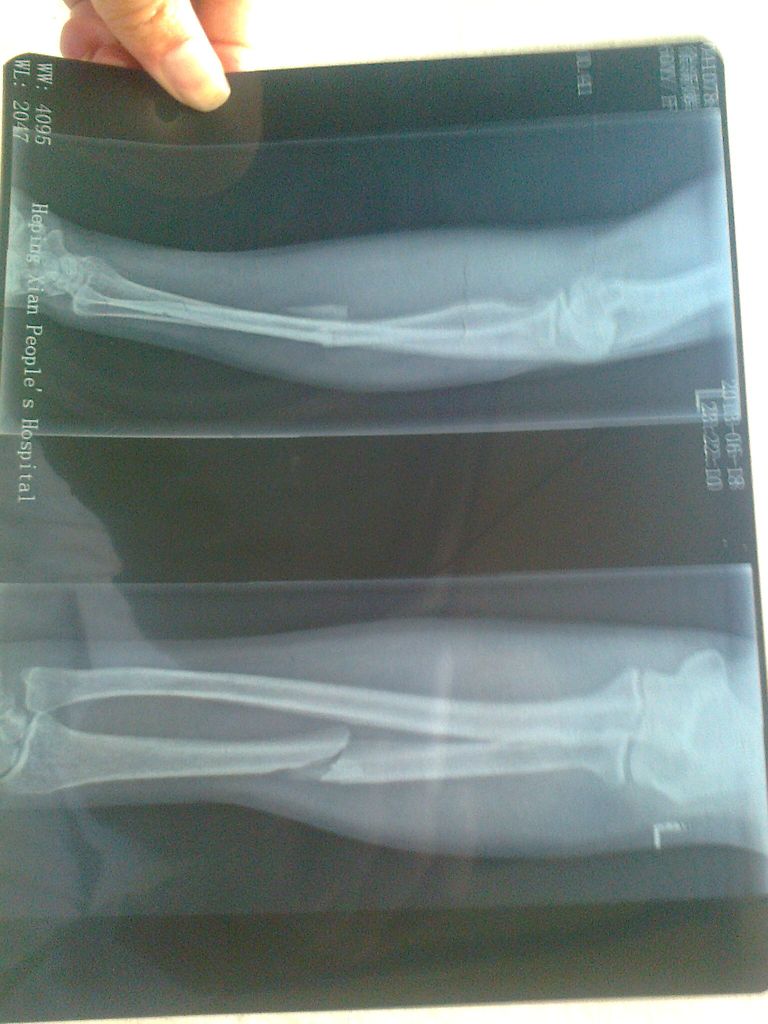

12013618号下午5点左右,60多岁的留守老人陈铭均/徐新娣夫妇去耕作责任田,准备育秧时,路过陈如胜/陈冠洲/林亚姜一家的责任田的田埂上时,陈如胜/陈冠洲/林亚姜一家喊打喊杀,围追堵截、持棍持械、打伤打残陈铭均/徐新娣夫妇。在此过程中,陈如胜年轻力壮,恶意把受害人徐新娣左手的手骨打断。受害人的骨折图片如下:

照片0875.jpg